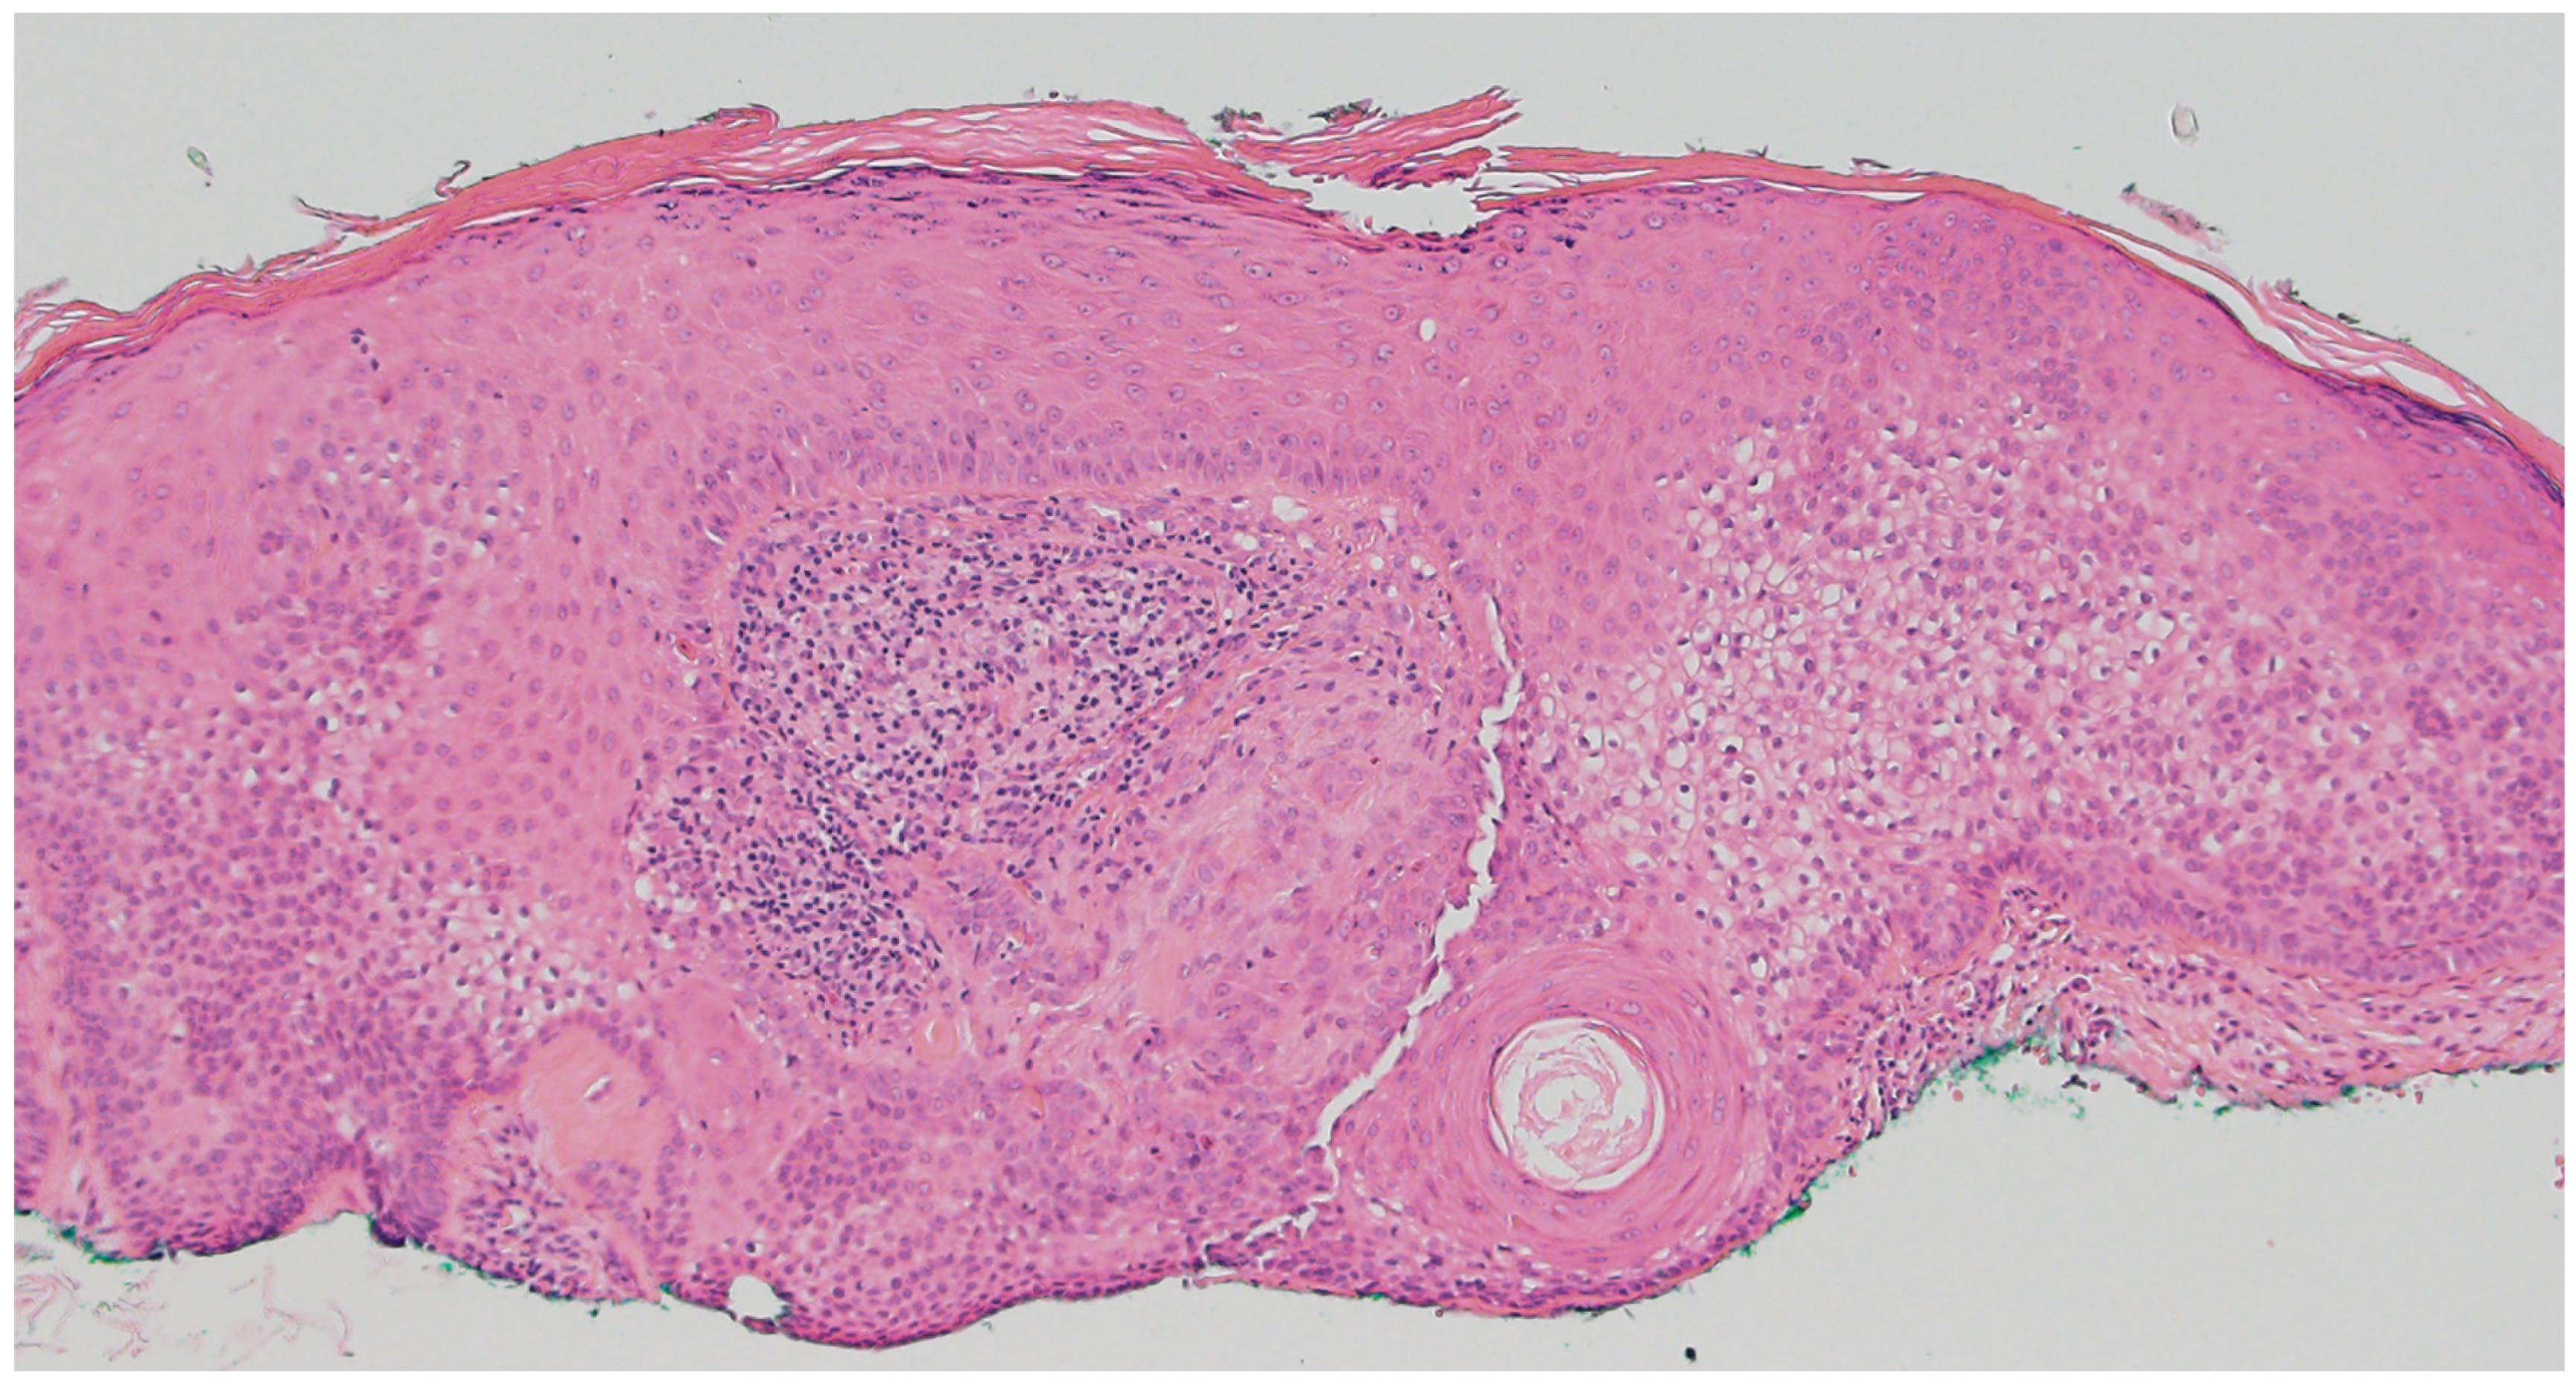

2.4. Trichoepithelioma

- Hernández-Núñez, A.; Nájera Botello, L.; Romero Maté, A.; Martínez-Sánchez, C.; Busquets, M.U.; Komáromy, A.C.; Martínez, J.B. Retrospective study of pilomatricoma: 261 tumors in 239 patients. Actas Dermo-Sifiliográficas 2014, 105, 699–705. [Google Scholar] [CrossRef]

- Neema, S.; Kashif, A.W.; Vasudevan, B. Dermoscopy of Pilomatrixoma. Indian Dermatol. Online J. 2023, 14, 450–451. [Google Scholar] [CrossRef] [PubMed]

- Thompson, L.D. Pilomatricoma. Ear Nose Throat J. 2012, 91, 18–20. [Google Scholar] [CrossRef]

- Alnaqshanbandi, S.M.; McAfee, J.L.; Ko, J.S.; Billings, S.D.; Ronen, S. Role of Immunohistochemistry in the Diagnosis of Pilomatrical Tumors. Am. J. Surg. Pathol. 2024, 48, 1543–1550. [Google Scholar] [CrossRef]

- Pujol, R.M.; Casanova, J.M.; Egido, R.; Pujol, J.; de Moragas, J.M. Multiple familial pilomatricomas: A cutaneous marker for Gardner syndrome? Pediatr. Dermatol. 1995, 12, 331–335. [Google Scholar] [CrossRef]

- Ciriacks, K.; Knabel, D.; Waite, M.B. Syndromes associated with multiple pilomatricomas: When should clinicians be concerned? Pediatr. Dermatol. 2020, 37, 9–17. [Google Scholar] [CrossRef]